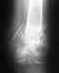

http://photofile.ru/express/indrarozatofanicorshtitha/ Мужчина, 35 лет, подвернул ногу на бегу. Отёк от растяжения небольшой, спадает. Ничего не болит, если не двигать ногой. Нога сейчас в полужёсткой повязке. Что будет без хирургического вмешательства? Какое может быть хирургическое вмешательство в данном случае? Мне предлагают вставить металлический штырь на целый год. Какие ещё возможны варианты?